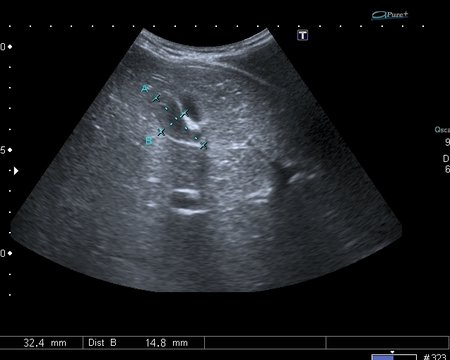

На УЗИ рядом с желчным пузырём определяется овоидное образование солидной струкутры с чёткими контурами.

Порекомендовал КТ, но в связи с наступающими новогодними праздниками и каникулами мальчик уехал домой и появился повторно через 2 месяца без жалоб для контрольного исследования. На УЗИ - картина осталась без динамики

Предположил наличие удвоения желчного пузыря, с этим заключением пациент исчез из поля зрения.